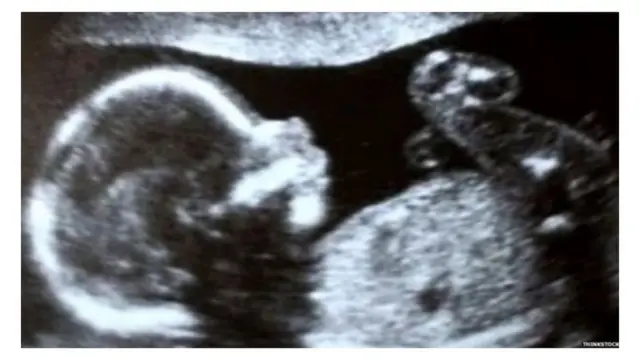

इमेज स्रोत, Thinkstock

इस क़ानून को 'हार्टबीट एक्ट' कहा जा रहा है और इसे प्रो-लाइफ़ समूह का समर्थन हासिल है. उनका मानना है कि इस क़ानून से कई बच्चे दुनिया में आ सकेंगे. इस क़ानून को हार्टबीट एक्ट इसलिए भी बताया जा रहा है, क्योंकि छह हफ़्ते में गर्भ में पल रहे भ्रूण में धड़कन आ जाती है.

मैक्स अस्पताल में प्रिंसिपल कंसल्टेंट और स्त्री रोग विशेषज्ञ, डॉ. भावना चौधरी का कहती हैं, ''अल्ट्रासाउंड करने वाली उच्च तकनीक की मशीनें छह हफ़्ते के भ्रूण में हार्टबीट का पता लगा लेती हैं, लेकिन इसका ये मतलब नहीं है कि एक महिला को गर्भपात कराने का अधिकार नहीं होना चाहिए.''